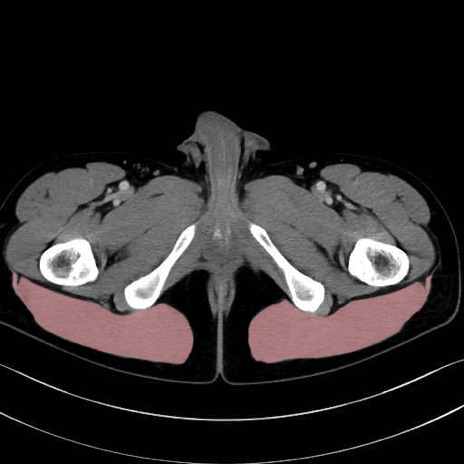

大殿筋 (Gluteus maximus)